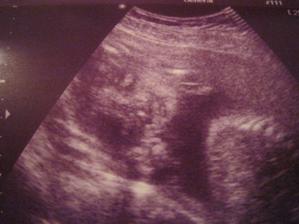

1.11.11 ko 29+1, Emisatko ma 1200g, dle biometrie je o cca tyden mensi (28+2), ale nozky ma delsi:D pry je porad v norme, plodovky ma dost, v cekarne radila, kdezto na utz mela pulnoc🙂 odebrana krev, CS 0, dalsi ko 22.11. a k 21.11. nastup na materskou🙂